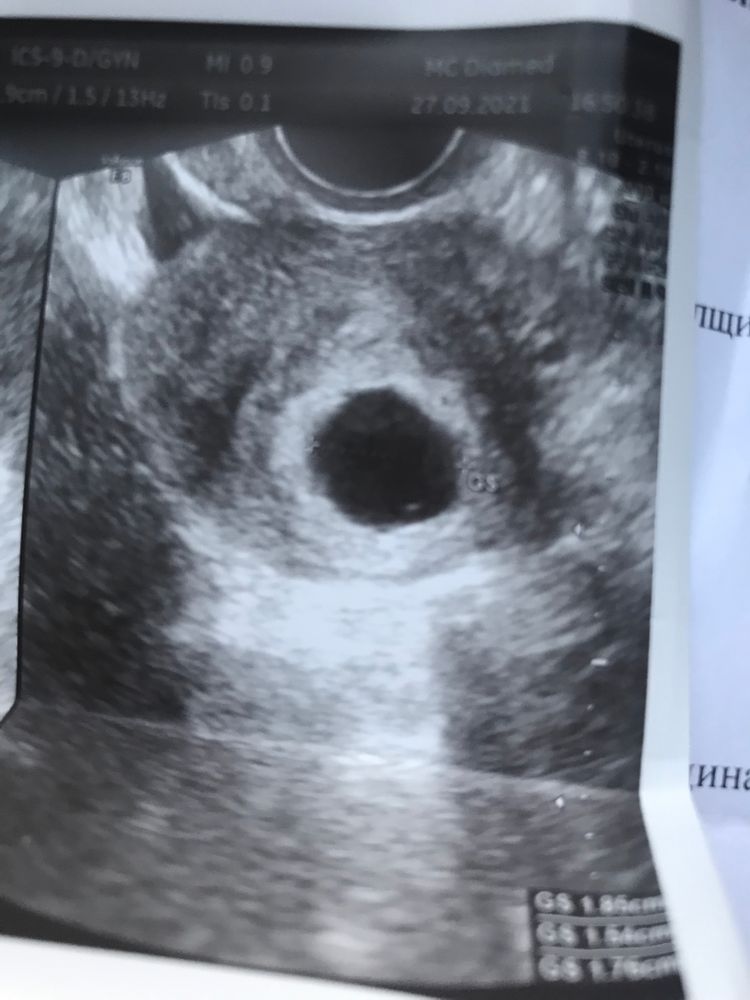

1.08. 21 была крайняя менструация, 09.09 сделала тест показал || довольно таки хорошие полоски, 20.09 сходила на первое узи, врач увидела ПЯ 12мм но не ЖМ, ни эмбриона нет.. в заключении написала, что 5-6недель, а то и 7? Сказала прийти через неделю, 27.09 (вчера) было повторное узи ничего не изменилось ПЯ выросло до 17мм, сказала идти на аборт, со слезами, забрала заключение и фото, пришла домой успокоилась увидела, что не совсем там пусто. Посмотрите пожалуйста фото. 🙏🏻 Мажущих выделений нет, скорее всего была поздняя овуляция, может стоит ещё подождать?

Плодное яйцо у вас, большое, вроде пустое, но с другой стороны, по моему я вижу маленькую точку. Подождите ещё недельку. Сходите повторно на узи. У некоторых эмбрион виден только, на 9 неделе, при поздней овуляции.

Оно пустое,даже жм не видно,у меня была анэмбриония,но был жм, поэтому и надежда была,а с пустым пя надежды мало,жм уже должен был быть в пя 12 мм ещё,при нормальной беременности в пя 8 мм был жм

Анэмбриония, наверное. У меня вот так же плодное яйцо росло, хгч рос отлично, а эмбриона не было и желточного мешочка. А то что там может видеться это хорион. Я на УЗИ, когда увидела, думала ну вот же эмбрион, а нет, увы.

Вроде как до 25 мм ПЯ ждут эмбрион. А у вас есть какие-то препараты в поддержке? Я бы в любом случае подождала. Даже если это и ЗБ, то может само выйдет, зачем сразу под нож?!

К сожалению там пусто. В жизни эмбрион 7 дней это огромный срок. И за это время должен был появиться не только ЖМ ,но и эмбрион с СБ. И аж 9 сентября был тест с //, с тех пор 20 дней прошло

В моем случае пя было 21 мм и совершенно пустое. Через неделю пя 28 мм и все появилось, включая эмбрион и сб.

Плохой рост ПЯ за неделю. Можете попробовать повторить узи у другого специалиста, но на вид пусто и рост плохой.